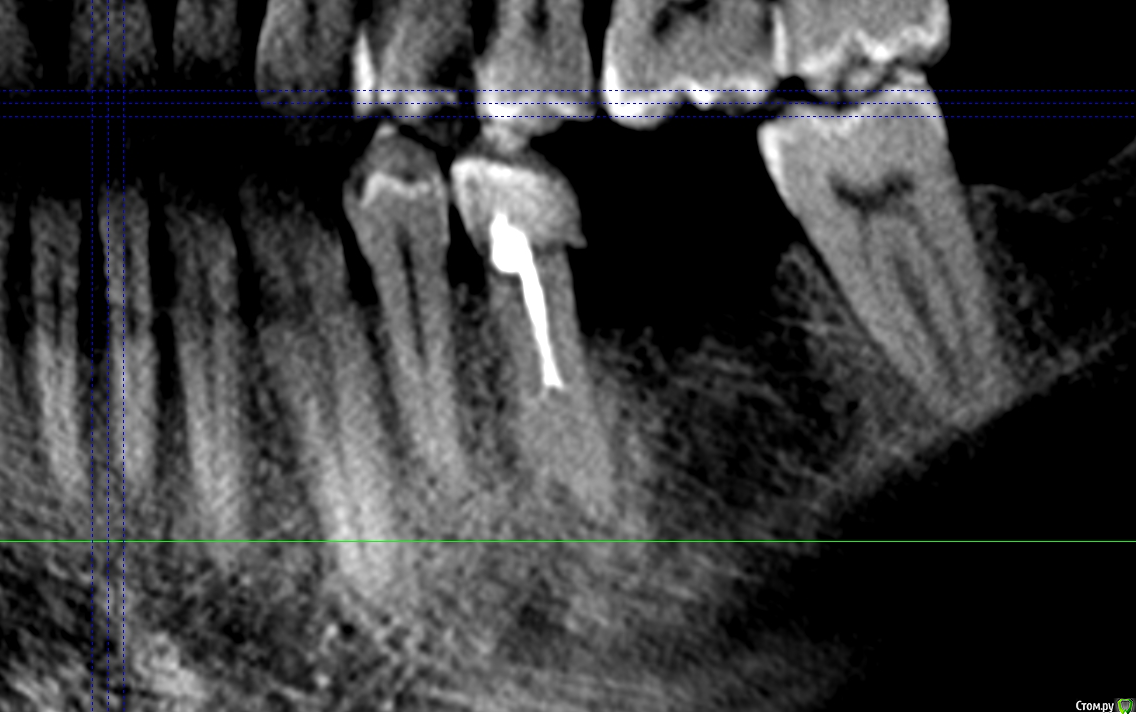

shurkne Опубликовано 1 мая, 2015 Поделиться Опубликовано 1 мая, 2015 (изменено) Здравствуйте!зуб 3.5Полтора года назад лечен резорцином(начал беспокоить...я как понимаю там периодонтитподскажите перелечивать его или удалять? Изменено 1 мая, 2015 пользователем shurkne Ссылка на комментарий

shurkne Опубликовано 13 мая, 2015 Автор Поделиться Опубликовано 13 мая, 2015 Начал перелечивать этот зуб!лечение проводилось под микроскопомврач смог пройти только 1 канал...второй смог пройти на половину(сказал все закаменело..можно перфорацию получить)в проходимый канал положили каласепт на 2 недели или больше Предложение дальнейшего лечениянепроходимый канал запломбировать чем то что замумифицирует каналв проходимый гутаперчу поделитесь вашими мнениями.... Ссылка на комментарий

shurkne Опубликовано 13 мая, 2015 Автор Поделиться Опубликовано 13 мая, 2015 Да он и не болел..... Просто на кт увидел периодонтит и решил довести зуб до ума.... А то потом бы заболел) Ссылка на комментарий